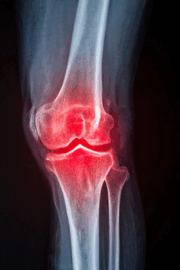

The Hidden Way Cold Weather Impacts Joint Fluid — And How to Protect Your Knees This Winter

Posted by: Reform Physical Therapy in Joint Health, Knee Pain, Seasonal Tips, Winter Wellness on December 4, 2025

Winter knee pain is extremely common in Maine, especially once temperatures start to drop. Many people notice more stiffness, soreness, or swelling throughout the season, but most don’t understand the real reason behind it. Much of this discomfort comes from the way cold weather changes the fluid inside your joints. This post breaks down the… Read More